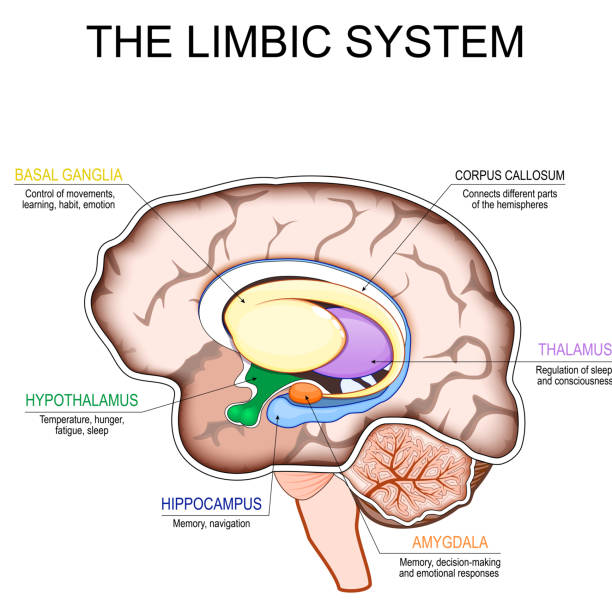

Коли ми отримуємо різке зауваження або стикаємося з осудом, першою реагує Амігдала — структура лімбічної системи, відповідальна за розпізнавання загроз.

Нижче зображення частин мозку, щоб більше уявити як все виглядає:

Також в мозку є Гіпокамп, він відповідає за:

Тому так і виходить, що при гострому стресі тимчасово знижується активність Префронтальної кори — області, відповідальної за:

Інсула — це центр інтероцепції, тобто здатності відчувати внутрішній стан тіла: серцебиття, напруження в грудях, стиск у горлі, нудоту, «клубок у животі», тепло/холод, внутрішнє тремтіння.